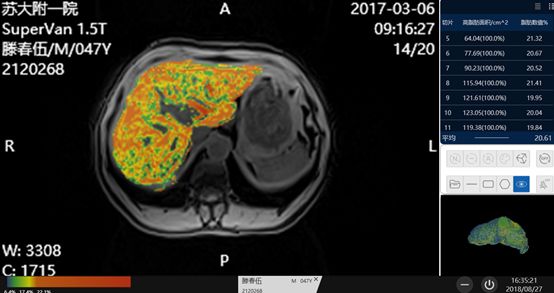

脂肪与铁双定量的技术更新至2.0版本,增加了组织区域自动分割,多区域量化的功能,后处理系统可以自动识别肝脏组织,并且剔除掉脉管系统,用不同的颜色来标注不同程度脂肪肝的区域,同时可量化每个层面重度脂肪肝的面积大小,并计算出平均的脂肪含量百分比,帮助我们更加直观的观察脂肪含量的情况。